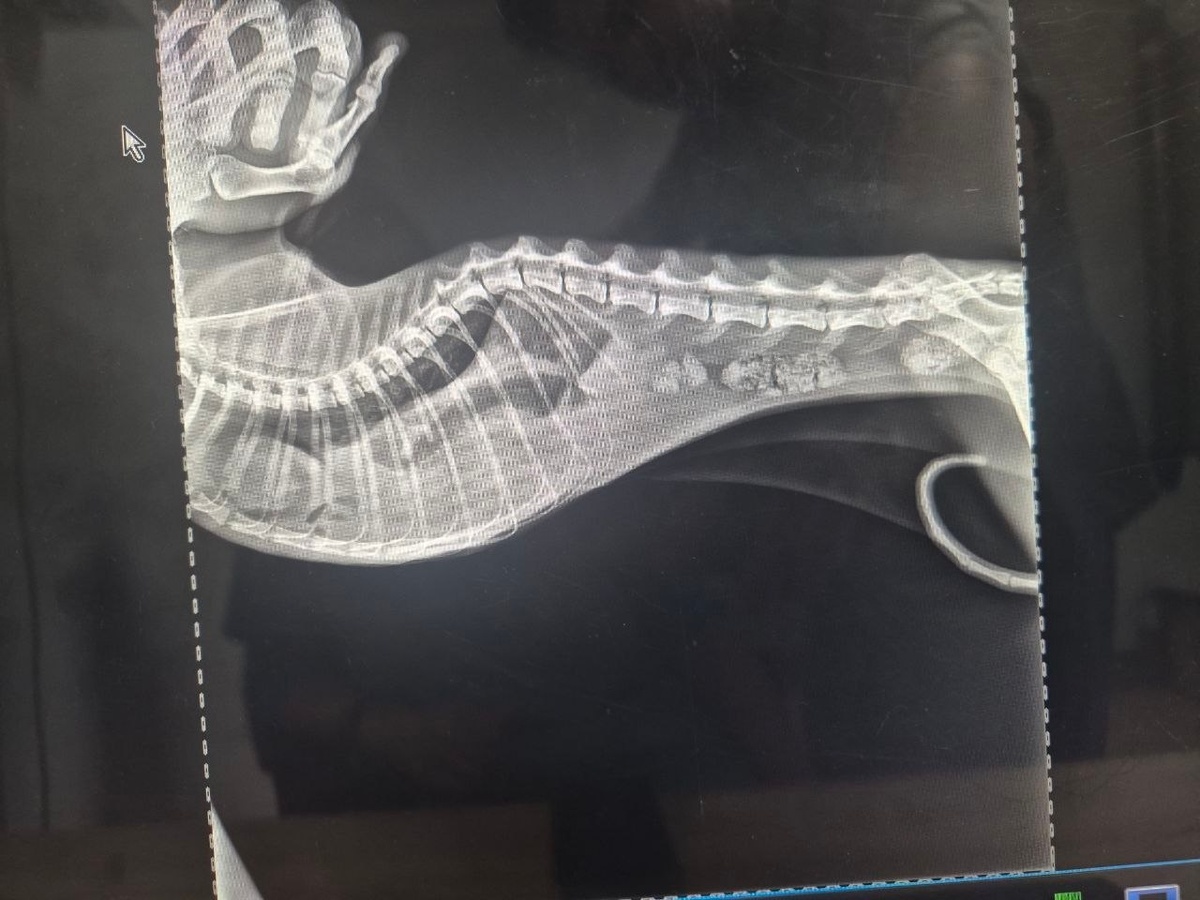

В ивановский приют попал котик, который не может есть из-за грыжи В приют «Майский день» попал очень больной котик. После каждого приёма пищи, он начинал задыхаться, судорожно кашлять и не мог сделать вдох. Его срочно обследовали в ветклинике и поставили серьезный диагноз – диафрагмальная грыжа. Это значит, что почти все внутренние органы из живота переместились в грудную полость и сдавливают его лёгкие и сердце. Поэтому ему нечем дышать. Каждая минута промедления может стоить животному жизни. Спасти его может сложнейшая дорогостоящая операция, которая вернет органы на место. Помочь котику можно в группе приюта. Фото: приют «Майский день»

В приют «Майский день» попал очень больной котик. После каждого приёма пищи, он начинал задыхаться, судорожно кашлять и не мог сделать вдох. Его срочно обследовали в ветклинике и поставили серьезный диагноз – диафрагмальная грыжа. Это значит, что почти все внутренние органы из живота переместились в грудную полость и сдавливают его лёгкие и сердце. Поэтому ему нечем дышать. Каждая минута промедления может стоить животному жизни.

Спасти его может сложнейшая дорогостоящая операция, которая вернет органы на место. Помочь котику можно в группе приюта.

Фото: приют «Майский день»